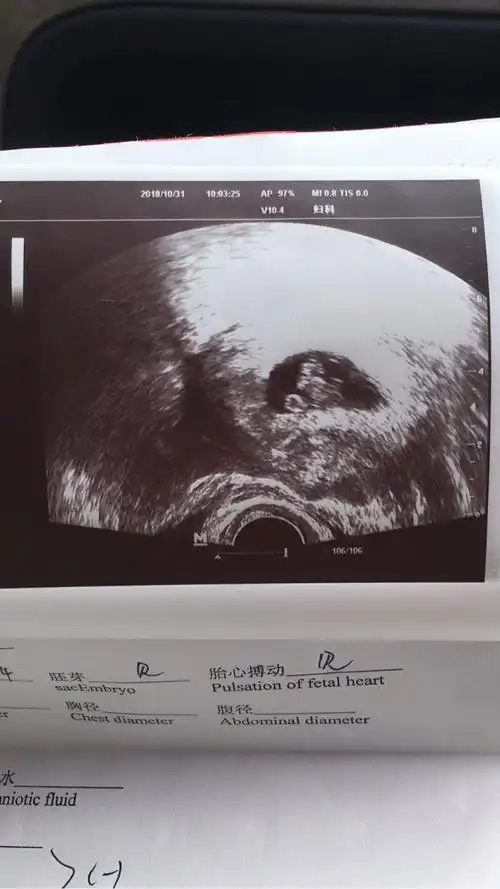

胎芽胎心

胎心胎芽

6 5查的胎心胎芽,孕囊偏大两周,孩子偏大一周,愿我的小宝贝健康平安

怀孕七周,今天做b超,检测胎心胎芽没问题,小肚子一侧疼,昨天下午开始